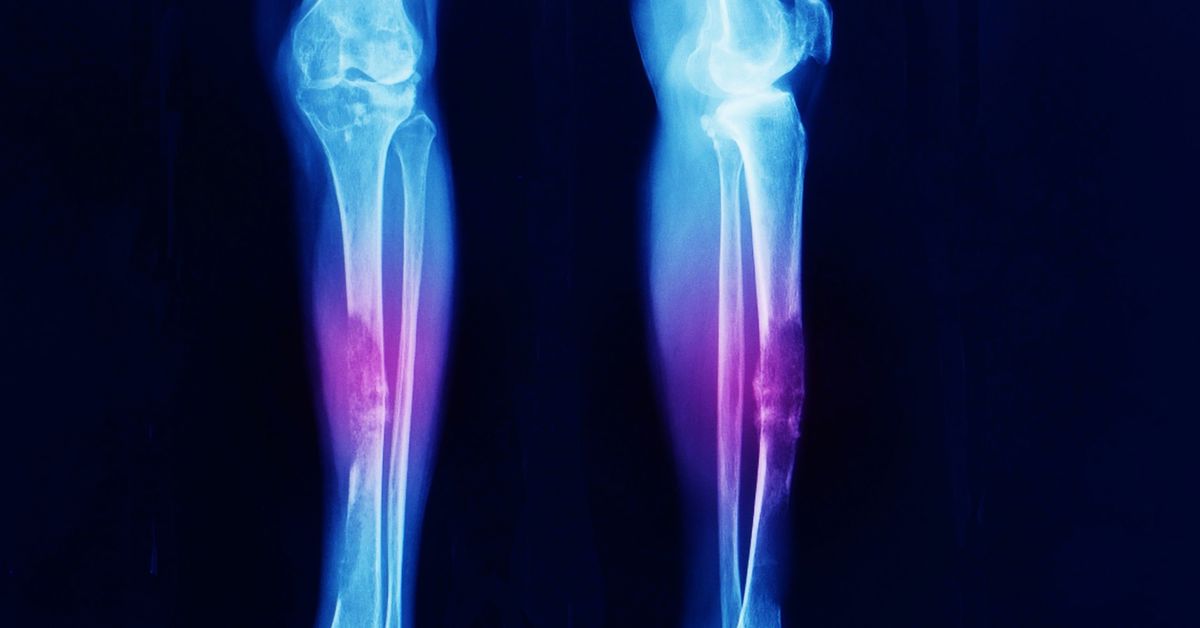

En sık görülen belirti şişliktir. Deri altında ele gelen kitle oluşur. Yumuşak doku tümörü durumunda bu kitle zamanla büyüyebilir. Ağrı her zaman görülmeyebilir. Ancak bazı hastalarda hassasiyet oluşur. Hareket sırasında rahatsızlık hissi artabilir. Kitle sert veya yumuşak olabilir. Bu durum tümörün yapısına bağlıdır. Belirtiler ciddiye alınmalıdır.

Yumuşak dokularda oluşan tümörler farklı yapıda olabilir. Kas yağ ve bağ dokusu etkilenebilir. Bazı tümörler iyi huylu olur. Bazı durumlar daha ciddi olabilir. Belirtiler zamanla ortaya çıkar. Şişlik en sık görülen bulgudur. Erken tanı önem taşır. Doğru tedavi planı süreci belirler. Uzman değerlendirmesi gereklidir.